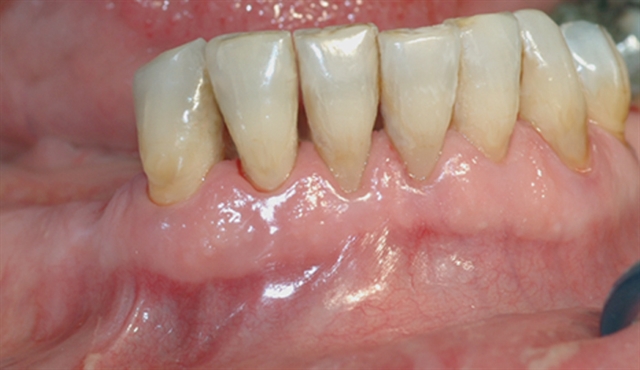

• Biletet viser tilsynelatande normale tannkjøttilhøve ved tenner i underkjeven.